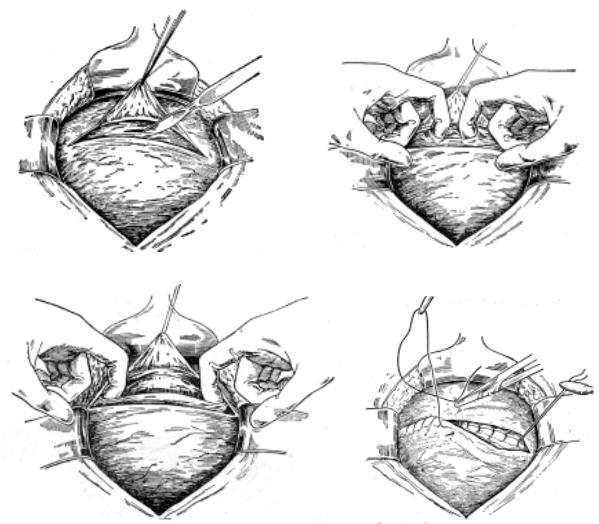

Современные методы лапаротомии и миомэктомии